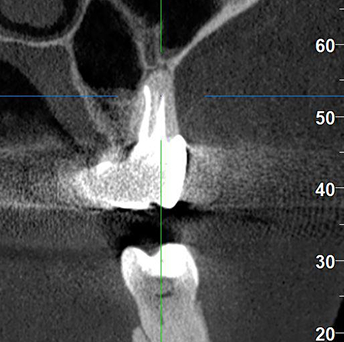

Лечение: Проведено эндодонтическое перелечивание зуба под дентальным микроскопом, что позволило точно выявить анатомические особенности корневых каналов и устранить последствия ранее некачественного лечения. После купирования воспалительного процесса (киста) каналы герметично запломбированы. Коронковая часть зуба восстановлена для сохранения функции и герметичности до этапа постоянного протезирования.

Результат: После проведённого лечения болевые ощущения полностью устранены, отёк щеки исчез, воспалительный процесс купирован. Зуб сохранён, восстановлена его функция. Установлена коронка, что позволило полностью восстановить анатомическую форму и жевательную эффективность зуба.